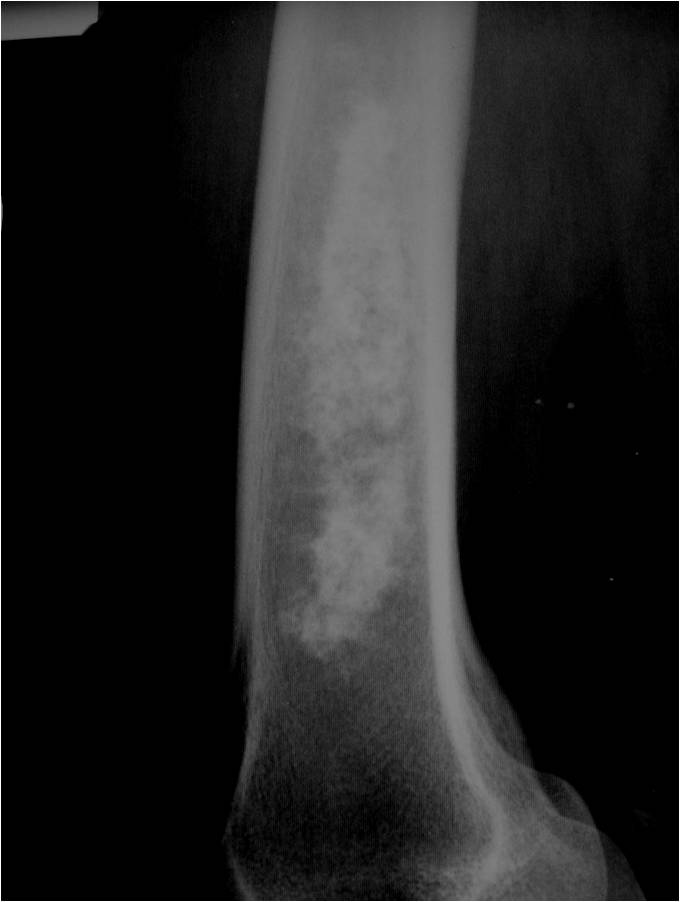

- Localized, radiolucent defect usually with punctate calcifications

- Calcifications are typical but not always present

- Matrix may demonstrate various degrees of calcification

- Calcifications are stippled, punctate, popcorn like calcifications and “Ring and Arc” calcifications

- Cartilage tumors grow in a lobular manner. The perimeters of the lobules undergo

- enchondral ossification that may calcify. If the entire perimeter of the lobule calcifies it appears

- radiographically as a “Ring”. If a portion of the perimeter of a lobule calcifies it forms an “Arc” on

- an X-ray.

Plain X-Ray:

- Geographic lytic lesion

- Central often metaphyseal in long bones

- Can be eccentric also

- Expansile remodeling with thinned cortex

- Chondroid matrix with calcifications in majority of tumors

- Approximately 20% have limited or no calcifications